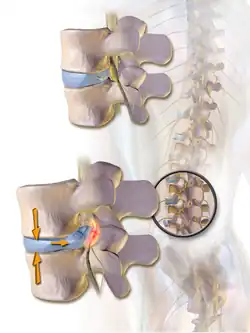

Spinal fusion is most commonly performed to relieve the pain and pressure from mechanical pain of the vertebrae or on the spinal cord that results when a disc (cartilage between two vertebrae) wears out (degenerative disc disease).[3] It is also used as a backup procedure for total disc replacement surgery (intervertebral disc arthroplasty), in case patient anatomy prevents replacement of the disc. Other common pathological conditions that are treated by spinal fusion include spinal stenosis, spondylolisthesis, spondylosis, spinal fractures, scoliosis, and kyphosis.[3]

The most common cause of pressure on the spinal cord/nerves is degenerative disc disease.[6] Other common causes include disc herniation, spinal stenosis, trauma, and spinal tumors.[4] Spinal stenosis results from bony growths (osteophytes) or thickened ligaments that cause narrowing of the spinal canal over time.[4] This causes leg pain with increased activity, a condition called neurogenic claudication.[4] Pressure on the nerves as they exit the spinal cord (radiculopathy) causes pain in the area where the nerves originated (leg for lumbar pathology, arm for cervical pathology).[4] In severe cases, this pressure can cause neurologic deficits, like numbness, tingling, bowel/bladder dysfunction, and paralysis.[4]